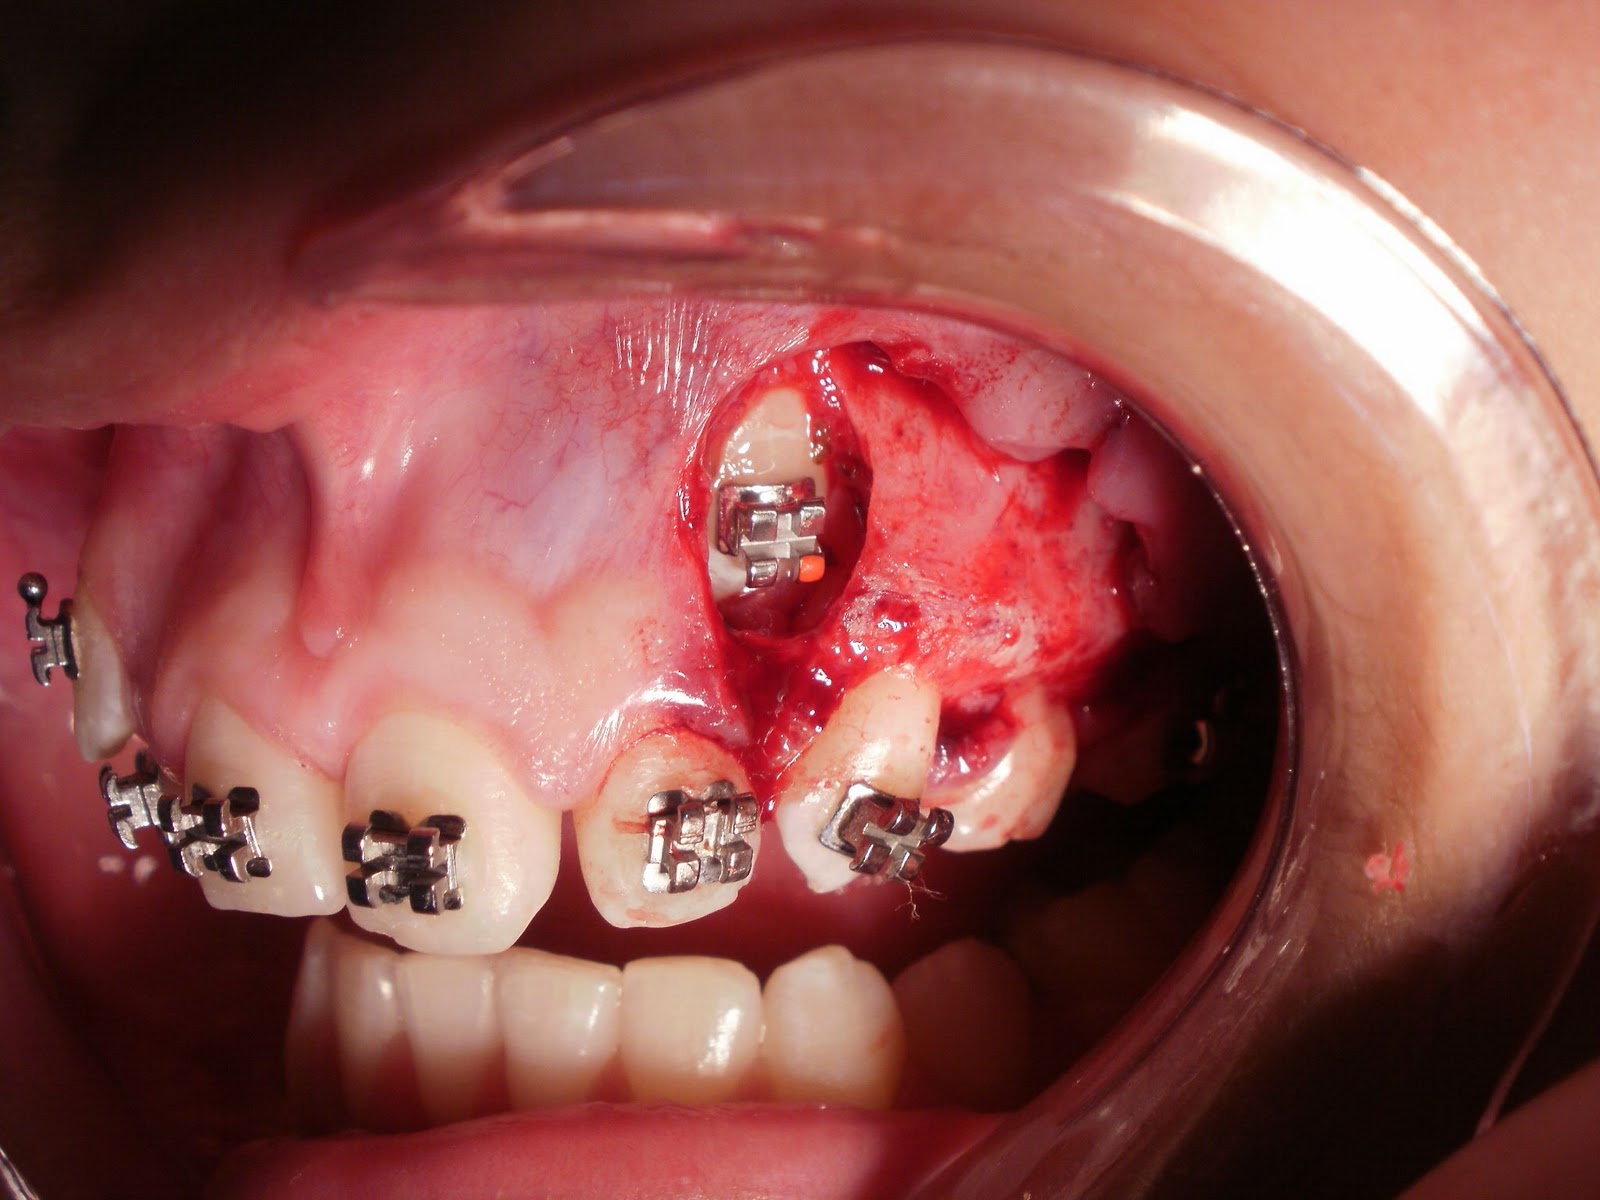

| Afastamento dos tecidos moles e acesso ao canino incluso e impactado |

| Opção pela colagem direta de braquete ortodôntico |

| Braquete Colado |